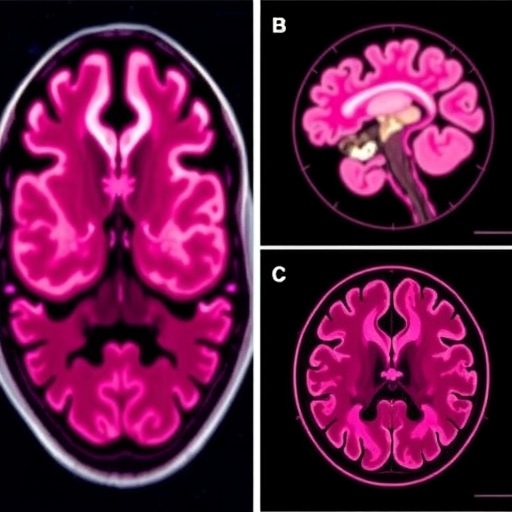

Following three cycles of treatment, the patient exhibited marked clinical improvements, evidenced by alleviation of neurological symptoms and regained functional independence. Magnetic resonance imaging (MRI) revealed appreciable reduction in tumor bulk within both the leptomeningeal spaces and brain parenchyma. Vasogenic edema and sulcal effacement, previously noted around the metastatic lesions, also demonstrated regression, highlighting the agent’s effectiveness in controlling aggressive CNS disease components.

Moreover, the interdisciplinary collaboration among oncologists, neurologists, radiologists, and pharmacologists was integral to the successful management of this case. Diagnostic precision through contrast-enhanced MRI facilitated accurate disease staging and response monitoring, illustrating the critical role of imaging biomarkers in contemporary oncology.